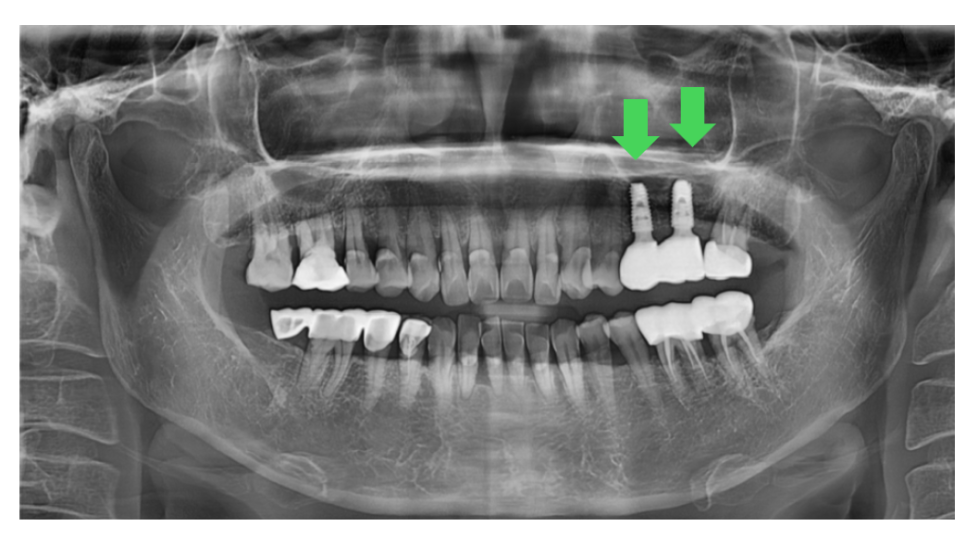

230803 픽스쳐 = 임플란트 = 치아 뿌리 부분

때문에 임플란트 1개 가격이 수술비만 포함된 것인지

보철과 기둥 비용까지 포함된 것인지 확인이 필요합니다.